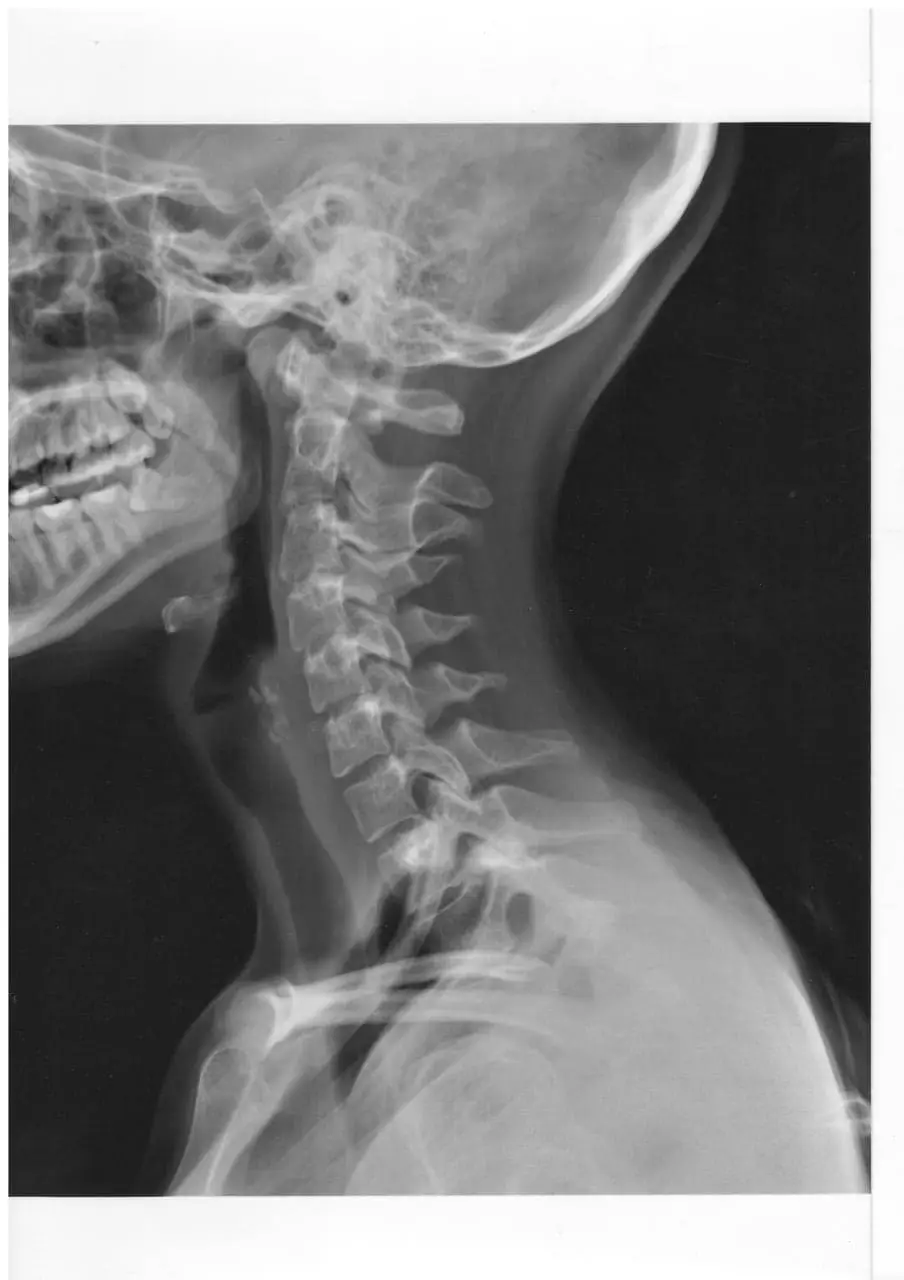

I went to a “well paid” clinic where the cold doctors (neurologist and ENT) barely looked at me and just ordered exams. The ENT doctor even asked me how much money I was earning to see how much they could charge me. I had an ultrasound of the neck vessels, x-rays of the neck, and an MRI of the brain. None of these tests revealed any pathology.

At that time, I learned that even these high-ranking doctors had no idea about what could cause such a terrible disease. I have attached the results of my examinations.

Of particular interest is the MRI of the brain (I cannot attach the images themselves in good quality, as they are on film). The conclusion indicates the localization of the “cystic” formations. The swelling was still visible ten days after the conflictolysis. I was terribly afraid of a possible diagnosis of a “brain tumor”; thank God it was not issued.

My testimony is accompanied by medical reports – MRI, X-ray, ultrasound – and protocols.